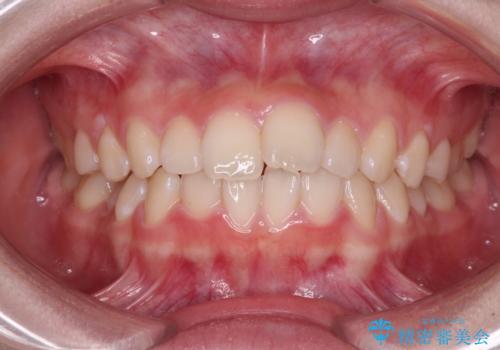

[ 再生治療・歯周外科・小矯正・セラミック補綴 ] 前歯の歯周病治療

担当医 大元洋佑

![[ 再生治療・歯周外科・小矯正・セラミック補綴 ] 前歯の歯周病治療の症例 治療前](https://seimitsushinbi.jp/wp/wp-content/uploads/2022/12/83065c2454a29ed71cf190e15a6106f4-500x350.jpg?v=1671673398)

![[ 再生治療・歯周外科・小矯正・セラミック補綴 ] 前歯の歯周病治療の症例 治療後](https://seimitsushinbi.jp/wp/wp-content/uploads/2022/12/ec16e37ee53325a6f6629b94759f5513-500x350.jpg?v=1671673454)